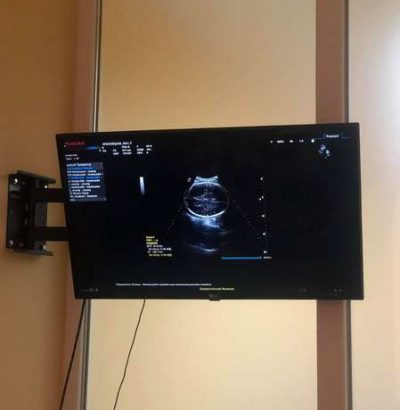

У комплексі з апаратом встановили принтер для друку зображень і виносний монітор для того, щоб пацієнти могли спостерігати за процесом дослідження, а вагітні – за оглядом своєї майбутньої дитини.